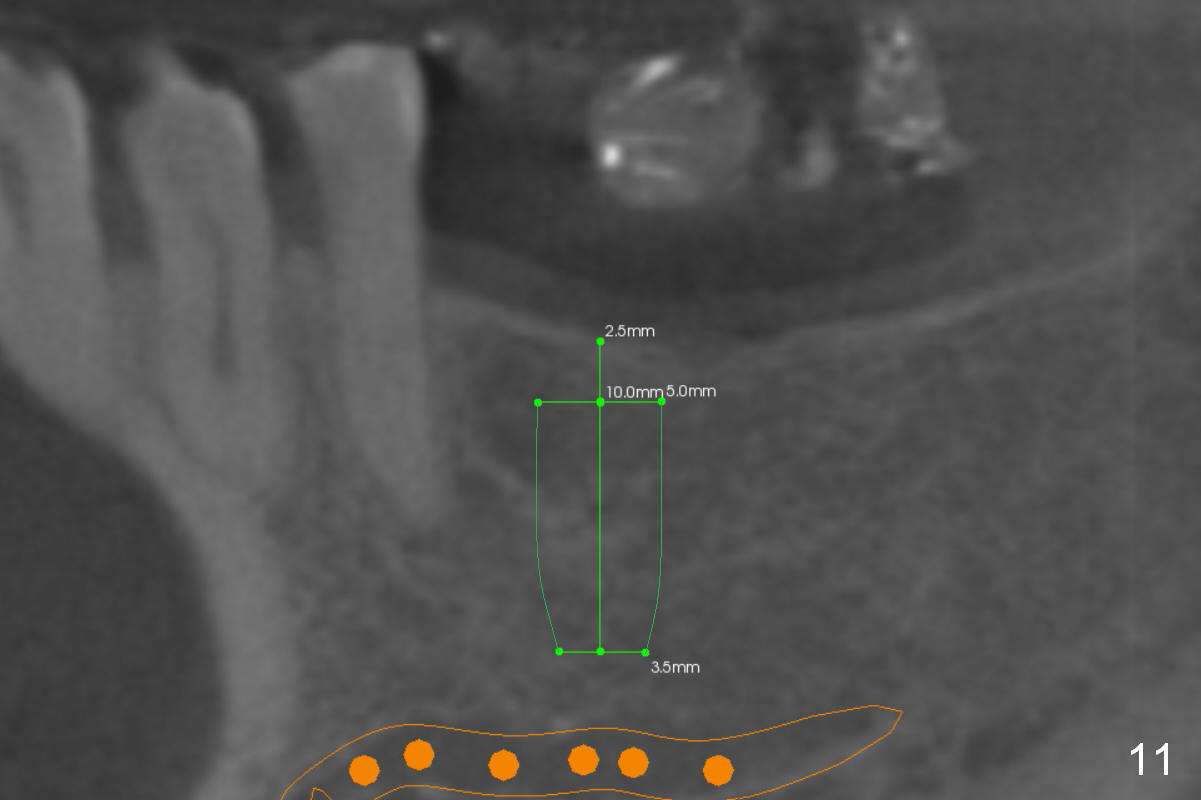

Without ridge split, the ridge top has to be trimmed (Fig.9 black area) to hold a 3 mm shorter implant (Fig.10,11).